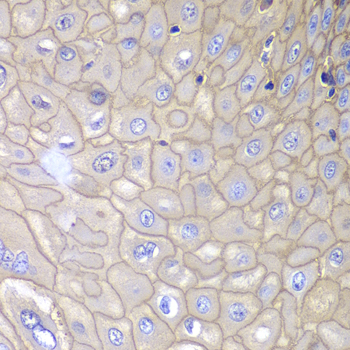

DescriptionANXA1 Polyclonal Antibody. Unconjugated. Raised in: Rabbit.

ApplicationWB, IHC, IF; Recommended dilution: WB 1:500 - 1:2000, IHC 1:50 - 1:200, IF 1:50 - 1:200